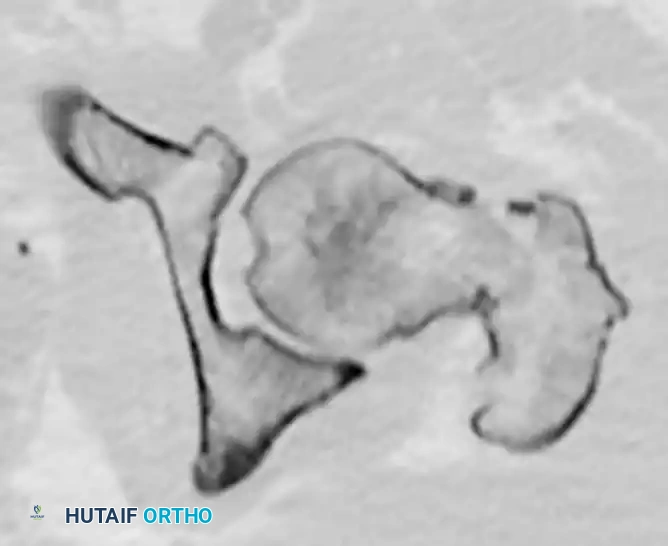

FIGURE 55-50: Rotation can be accurately assessed by comparing the contour and profile of the affected lesser trochanter to that of the contralateral, uninjured hip under fluoroscopy.

2. Projection of the Lesser Trochanter: In posterior dislocations, the lesser trochanter may not be seen because of the internal rotation of the extremity. In anterior dislocations, the lesser trochanter may be seen in its entirety due to external rotation.